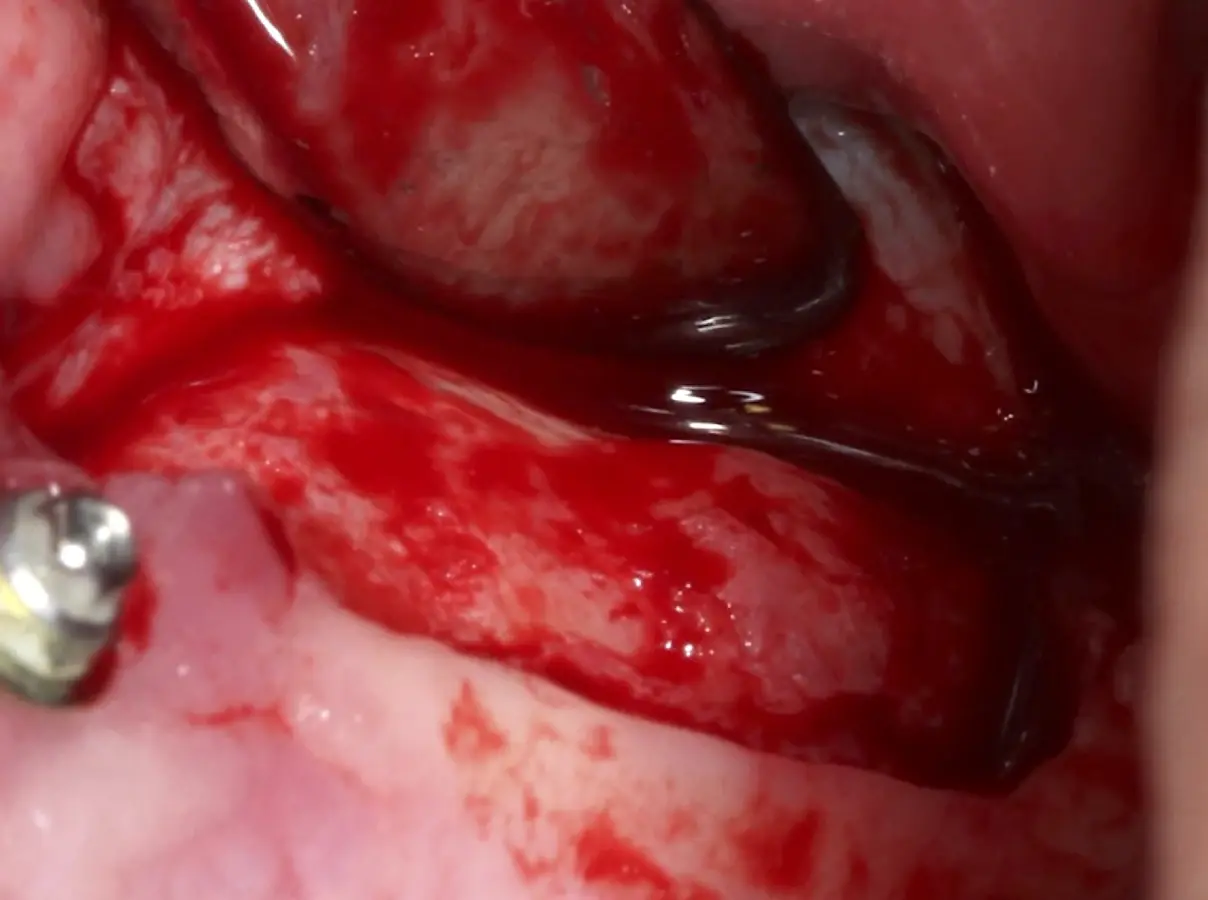

El tipo de inserto a ser utilizado dependerá del espesor de la pared ósea. Si la pared es menor a 0.5 mm, es mejor utilizar insertos de desgaste para prevenir la ruptura de la membrana de Schneider; si el espesor es mayor a 0.5 mm, se puede utilizar insertos de corte de espesor medio (Figura 3).

El clínico puede retirar la tabla ósea o introducirla como “tienda de campaña” dentro del seno maxilar. En cualquiera de las alternativas, es importante evaluar la presencia de tabiques óseos y de la arteria postero alveolar superior.